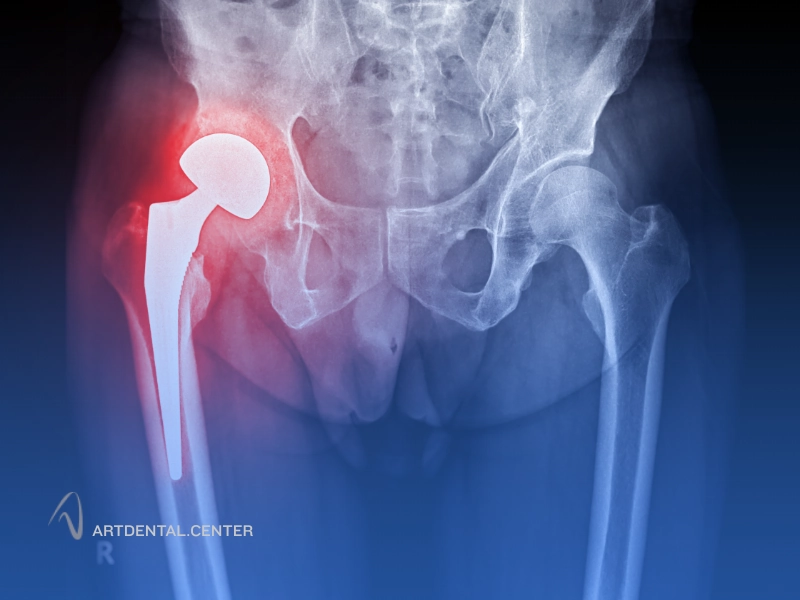

پیوند استخوان کف لگن برای فک

در برخی بیماران که تحلیل استخوان فک شدید است یا حجم کافی برای کاشت ایمپلنت دندان وجود ندارد، استفاده از استخوان خود فرد بهترین گزینه درمانی است. یکی از منابع اصلی برای این نوع پیوند، استخوان کف لگن (ایلیاک کرست) است. این روش که به عنوان پیوند استخوان اتولوگ شناخته می‌شود، با موفقیت بالا پایه‌ای محکم برای ایمپلنت‌ها ایجاد می‌کند و روند بهبود استخوان طبیعی فک را تسریع می‌کند.

پیوند استخوان کف لگن برای فک چیست؟

پیوند استخوان کف لگن شامل برداشت مقداری استخوان از ناحیه لگن و انتقال آن به فک است. این استخوان غنی از سلول‌های زنده است و قابلیت بالایی در جوش خوردن با استخوان فک دارد. معمولاً این روش زمانی توصیه می‌شود که تحلیل استخوان فک بسیار شدید باشد یا سایر روش‌های پیوند استخوان مصنوعی کافی نباشند.

مراحل انجام پیوند استخوان کف لگن برای فک

• مشاوره و معاینه کامل: بررسی میزان تحلیل استخوان فک با استفاده از سی‌تی اسکن سه‌بعدی.

• برداشت استخوان از لگن: جراح با دقت استخوان مورد نیاز را از ناحیه ایلیاک کرست برداشت می‌کند.

• پیوند استخوان به فک: استخوان برداشت شده به ناحیه فک منتقل شده و با پیچ یا فیکساتورهای مخصوص تثبیت می‌شود.

• بهبود و جوش خوردن استخوان: طی چند ماه، استخوان پیوند شده با استخوان فک ادغام شده و آماده کاشت ایمپلنت می‌شود.